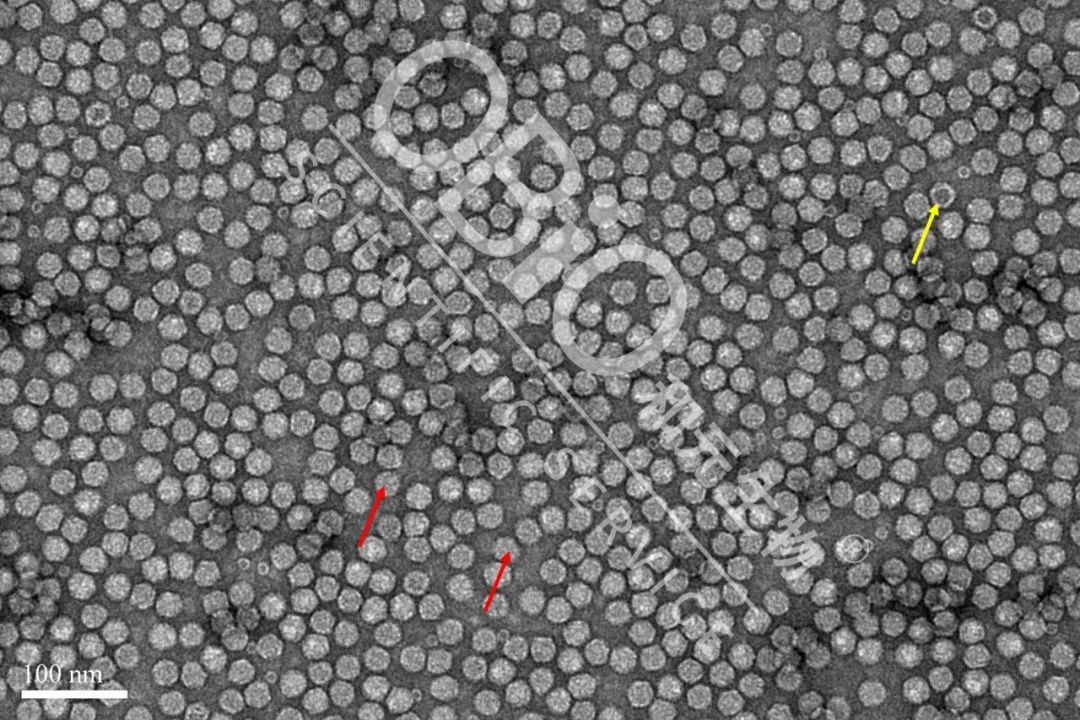

图2 银河集团官网 生物制品rAAV形式加工空壳率

电镜結果:内包装DNA基因遗传组的疫情粉末状肥料为方形粉末状肥料(网红箭头符号符号);空疫情粉末状肥料中部的存在洞(紫色箭头符号符号)